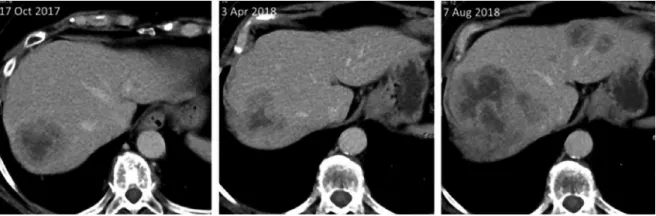

2017年10月,患者出现呼吸困难、咳嗽。胸部CT显示肺部、肝脏和淋巴结有多个可疑肿物。转诊乳腺癌科,行腹部CT和骨骼扫描完成分期。肝内多个53 × 45mm大小可疑肿物。有骨转移。抽血显示肝酶正常;体积描记显示失代偿性碱中毒、低氧血症、轻度梗阻和无限制性。

开始治疗近9个月后,行胸部和腹部CT以及头部MRI分期,结果显示:除肺和脑的病情稳定(图2),肝脏(8×10 cm)(图3)和颅骨观察到病情明显进展。肝活检证实激素受体阳性(ER 80%,PR 10%)和HER2阴性的乳腺癌转移,Ki-67为25%。就进一步的治疗方案与患者交流,并建议更换药物。患者因担心脑转移瘤希望继续使用ribociclib和芳香化酶抑制剂进行治疗,而在整个治疗过程中,脑转移瘤一直状态稳定。由于患者一般情况恶化,停止服用ribociclib,单独继续服用阿那曲唑。2个月后,下一阶段结果显示显示:除大脑外,所有转移部位都有进展性疾病。行肝动脉化疗栓塞术治疗肝转移瘤后,开始紫杉醇化疗。3个周期化疗的临床疗效良好,肝、肺部分缓解,脑部病变稳定。

图3.肝转移瘤CT表现